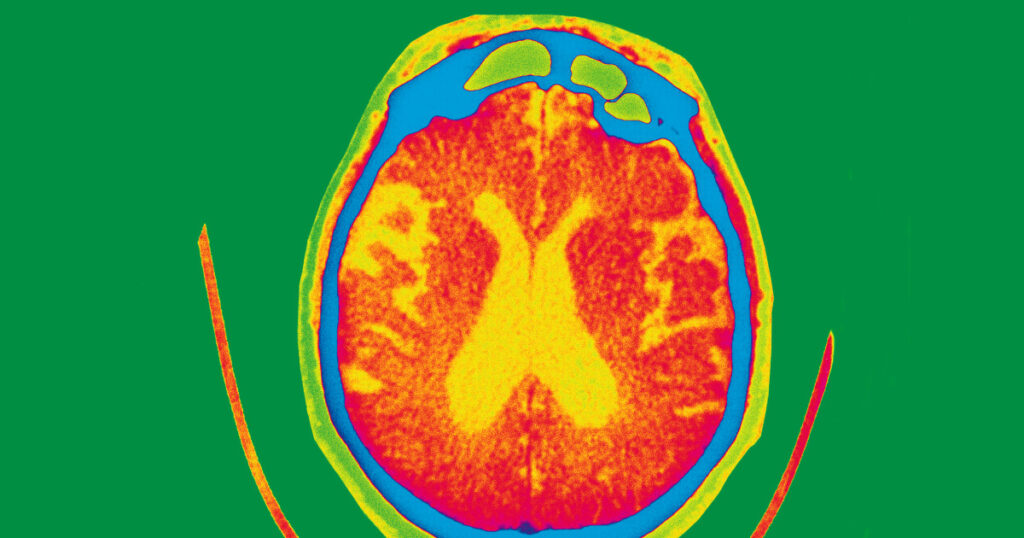

The FDA cleared the drug for use in adults with mild cognitive impairment or early Alzheimer’s disease, the drugmaker said. Kisunla works by targeting amyloid in the brain, considered a hallmark of Alzheimer’s disease.